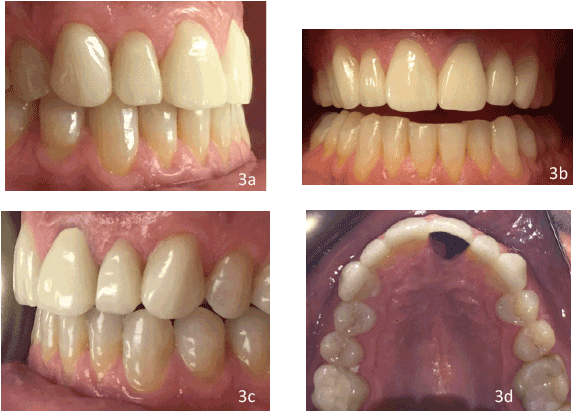

治疗

治疗方案包括拆除现有的修复体和腐蚀#6-11,评估基础桩和芯#9的状况,使用压制的单片二硅酸锂贴面#6、7、8、10、11和金属烤瓷#9进行修复。由于患者有磨牙病史,9号选择金属舌而不是瓷舌(图3d)。

插入

从实验室返回后,对模型进行了5个单板和1个冠的贴合度和颜色一致性检查。临时修复被拆除,牙齿被用浮石浆清洁以清除任何碎屑。永久性修复尝试和检查适当的配合,边缘精度,接触,阴影和整体美学。最终修复体#6-11的内表面用35%磷酸预处理20秒,彻底清洗,干燥,然后硅烷化60秒,并让其干燥。第6-11颗牙齿被很好地隔离,用35%磷酸治疗15秒,冲洗并轻微干燥。隔离是重做。两瓶胶粘剂(全胶粘剂)混合后,用空气稀释。单片二硅酸锂贴面#6、7、8、10、11使用树脂胶结(选择2),与高贵金属金属冠#9使用树脂改性玻璃离聚体胶结(FujiCem)(图3a-3d)。清除多余的水泥,重新检查触点。检查咬合以获得正确的犬类指导,并拍摄最终照片。 In the next visit, a lab fabricated occlusal guard was delivered after adjustment was made to ensure proper canine guidance in all excursive movements.

图3:a)术后右侧视图b):术后正面视图c):术后左侧视图d):术后上颌视图

没有一种材料对每种情况都是理想的,因为每种材料都有优缺点。在本病例中,使用两种不同的材料修复了6颗上颌前牙,达到了患者和临床医生满意的笑容修复(图4)。